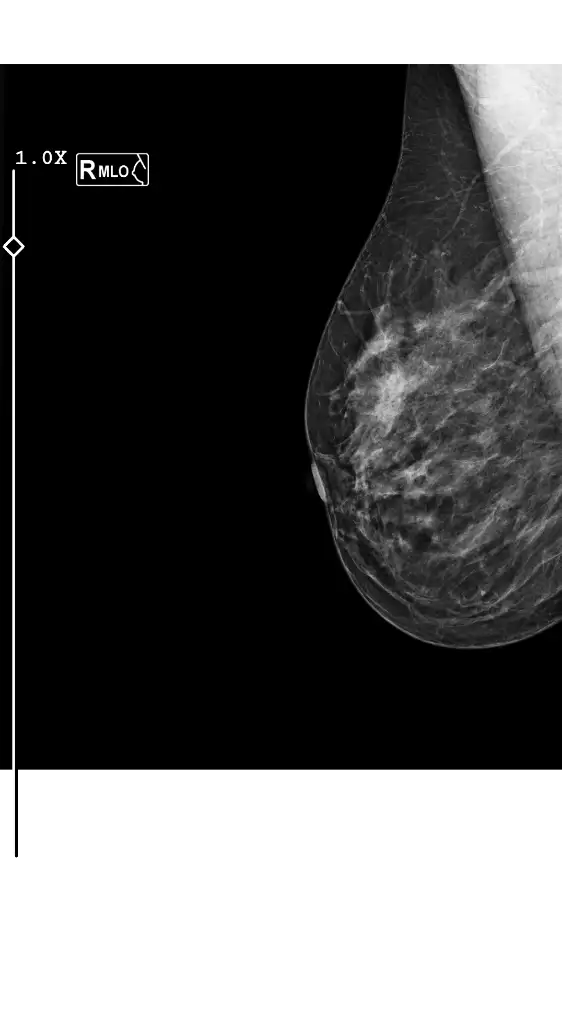

Eklentiler

• 1000181881.webp

1000181881.webp

12,3 KB · Görüntüleme: 110